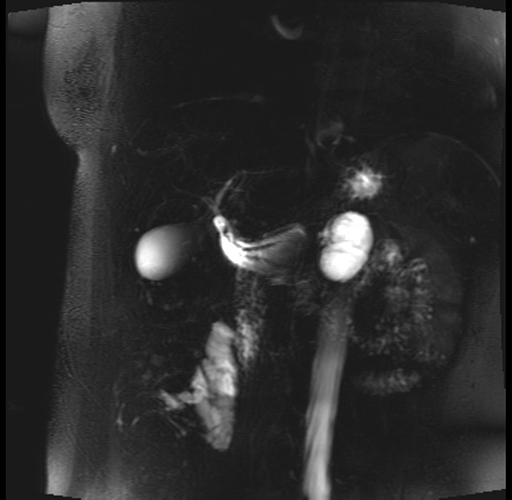

Imaging Analysis

Look through the patient's CT scan to identify any areas of concern for the necessary procedure.

Based on your CT findings, which issue(s) are present and would give reason for "planned slowing down moment(s)" in this case?

Considering a standard distal pancreatectomy procedure, what step(s) of the operation would you do differently in this case?